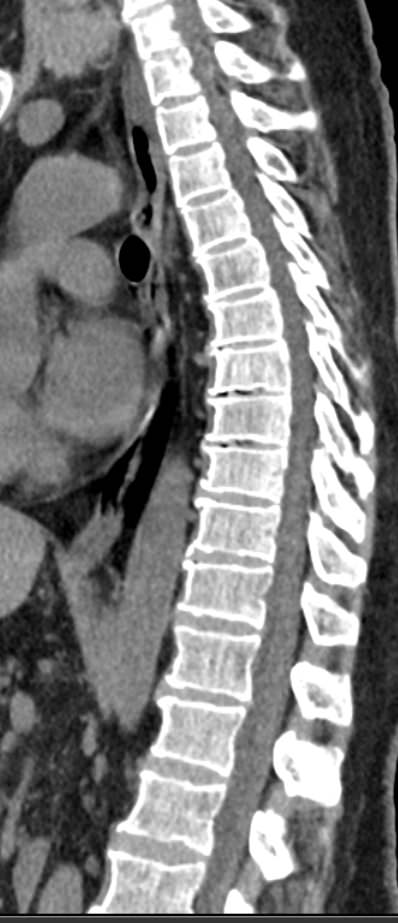

Для диагностики даже незначительных патологических изменений в различных отделах позвоночника, особенно в случае распространенного поражения, применяется один из современных наиболее информативных методов обследования – мультиспиральная компьютерная томография всего позвоночника. Методика основана на использовании проникающей способности рентгеновских лучей через органы и ткани человека и позволяет получить подробное изображение всех структур позвоночного столба. В комплексное обследование входит исследование шейного, грудного, пояснично-крестцового отделов позвоночника и копчика.

В медицинских центрах «Доступная медицина» сканирование всего позвоночника выполняется на новейших мультиспиральных компьютерных томографах последнего поколения TOSHIBA AQUILION в различных модификациях. Особенностью данных аппаратов является их способность проводить от 64 до 128 тончайших срезов одномоментно с минимальной толщиной от 0,5 мм.

Увеличенное количество высокочувствительных детекторов, которыми оснащены томографы, позволяет получать послойные снимки высокого качества с большой скоростью. Эта особенность данных аппаратов обеспечивает быстроту выполнения сканирования. При этом пациент получает минимальную дозу облучения, что имеет важное значение, особенно при такой обширной зоне исследования, как позвоночный столб.

- патологические изгибы позвоночника, сколиоз, усиленный или выпрямленный лордоз как нарушение статической функции позвоночника;